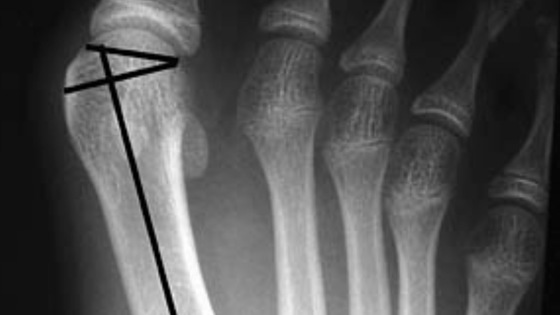

Но повлиять на появление вальгусной деформации стопы могут травмы, особенно у спортсменов. Это может привести к разрывам сухожилий и травмам костей. Этот фактор — предпосылка к образованию шишки в месте перелома плюсневой кости.

А способ избавиться от шишки на ноге один — операция. Только так можно выздороветь и избавиться от боли.

«Если вы думаете, что про шишку на ноге можно просто забыть, достаточно поносить некоторое время ортопедические стельки, то глубоко заблуждаетесь. Последствия вальгусной деформации могут быть крайне неприятными. Прежде всего, это резкая боль при ходьбе и, как результат, стеснение движений. Согласитесь, никто в такой ситуации не готов это постоянно терпеть. Поэтому я как врач вижу единственный выход — в хирургическом удалении шишки», — подчеркнул специалист.